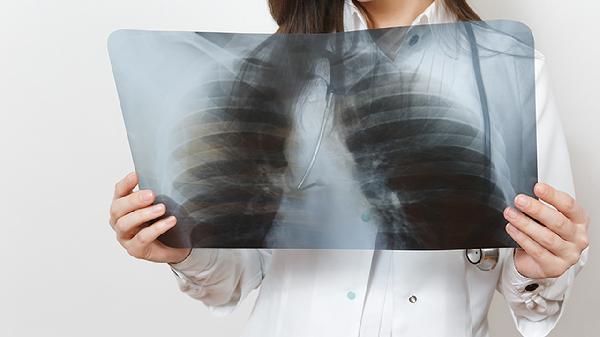

成人患肺结核的症状主要有咳嗽、咳痰、咯血、胸痛、发热等。肺结核是由结核分枝杆菌感染引起的慢性传染病,主要通过呼吸道传播,建议患者及时就医,在医生指导下进行规范治疗。